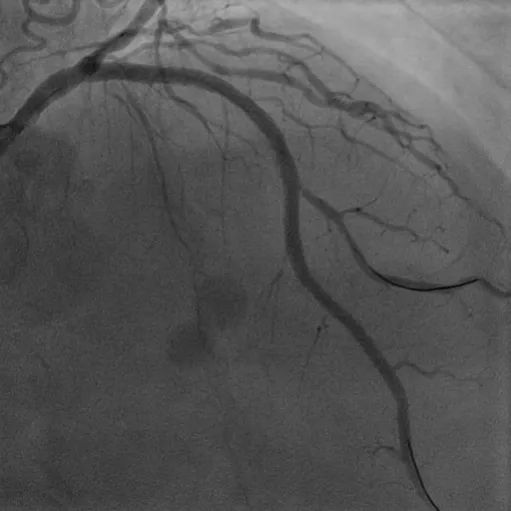

LM-LAD钙化病变:患者73岁女性,主因胸痛2小时入院,既往高血压病史,诊断不稳定型心绞痛。该患者1周前因心绞痛入院,CAG显示RCA95%狭窄伴血栓,于RCA植入一枚支架。患者左主干严重钙化病变狭窄80%,合并LAD弥漫钙化最重处狭窄90%,精准充分预处理格为重要,姚朱华主任团队综合评估患者病情后决定择期IVUS指导下行Shockwave冲击波球囊治疗。IVUS检查显示LM-LAD弥漫性钙化,最重处360°环形钙化,应用3.5*12mm Shockwave冲击波球囊顺利到达病变处,自LAD中段至LM末端连续释放脉冲,在左主干处释放4个周期(40个脉冲),成功于LM-LAD植入3枚支架,术后IVUS评估达到理想的支架膨胀及贴壁效果。

术前冠脉造影

植入支架后